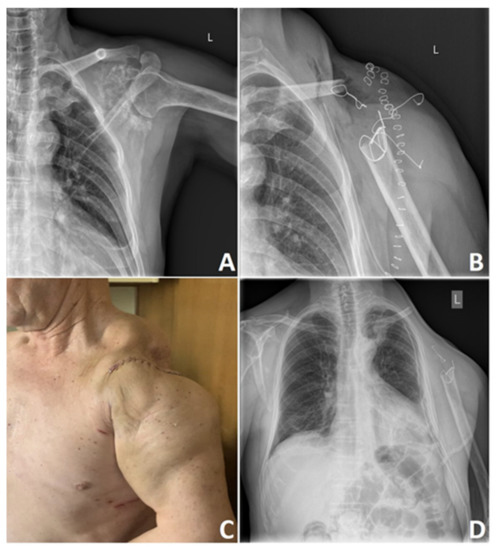

5. Surgical Treatment of Chondrosarcoma